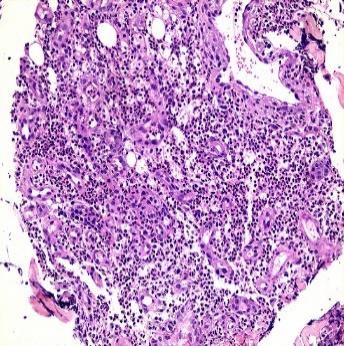

在之后的诊治中,患者病情继续好转。使用激素治疗后第3天,病损范围停止增长(图 5)。第17天,大部分创面已干燥结痂并生长出新鲜皮肤组织(图 6)。第35天,患者激素已逐渐减量至28 mg/d口服,绝大部分创面已干燥结痂,新鲜皮肤下可见青紫色血管影,原手术切口已基本愈合(图 7)。此外,病理回报送检组织除大量中性粒细胞浸润外未见异常(图 8)。患者以“手术后型PG”为诊断出院,继续口服用药并随访2周后告知创面完全愈合。

| 图 8 送检组织病理切片(15×20) |

目前,并没有针对手术后型PG的相关诊治指南。对于该病的诊断,多参考Su等[5]于2004年提出的经典溃疡型PG的诊断标准(见附表1)。该方案的主要诊断依据为临床表现与病理活检。但应特别指出的是,PG的病理表现除大量中性粒细胞浸润外并无特异度,仅为排除性诊断。